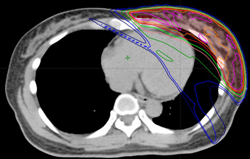

此外,由於螺旋刀無須使用等中心(ISO-Centric)的概念,又應用360度全方位調強的特性,因此劑量均勻分佈,比傳統IMRT更加優勝,對重要器官影響也更少。以下圖的乳房治療為例,螺旋刀能造出更好的弧形劑量分佈,以適合胸部 / 乳房的形狀,而肺部,心臟的劑量更少,減低後遺症。

除乳癌外,螺旋刀亦適合肺癌、肺膜腫瘤、前列腺癌、鼻咽癌、食道癌等。對於複雜外形腫瘤,多病灶轉移,腦及脊髓神經系統電療,或腫瘤復發需要作二次電療,尤為適合。